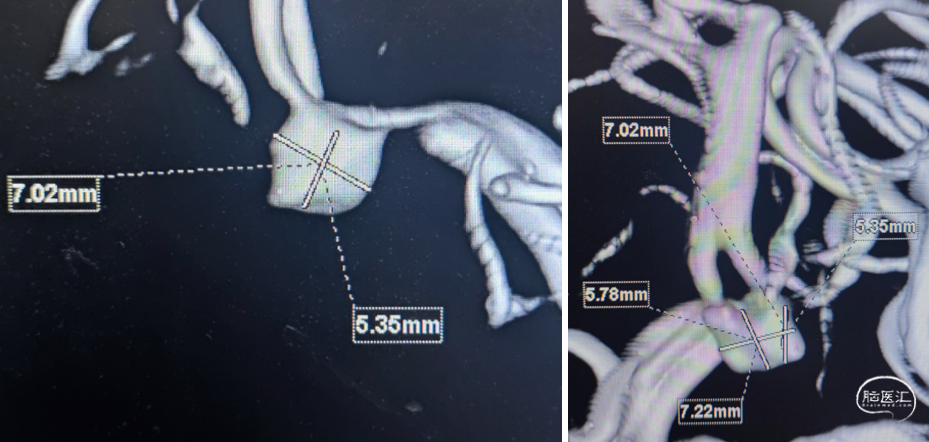

微导管3D评估动脉瘤与载瘤动脉关系

WEB选择:理想SL9x3(没有),选择SL8x4

直接测量:7.4x3.92mm

3D测量:7.22x5.35mm

对比测量:8.9x4.8mm(偏大10%)

平均宽度(4.5+3.8)=4.2mm,最小深度7.5mm,选择SL5x3

右侧:平均宽度(5.5+3.9)=4.7mm,最小深度2.8mm,选择SL5x2

3D测量动脉瘤:宽5.8mm,深5.1mm,SL6x3

平均宽度(4.7+3.5)=4.1mm,最小深度3.4mm,选择SL6x2